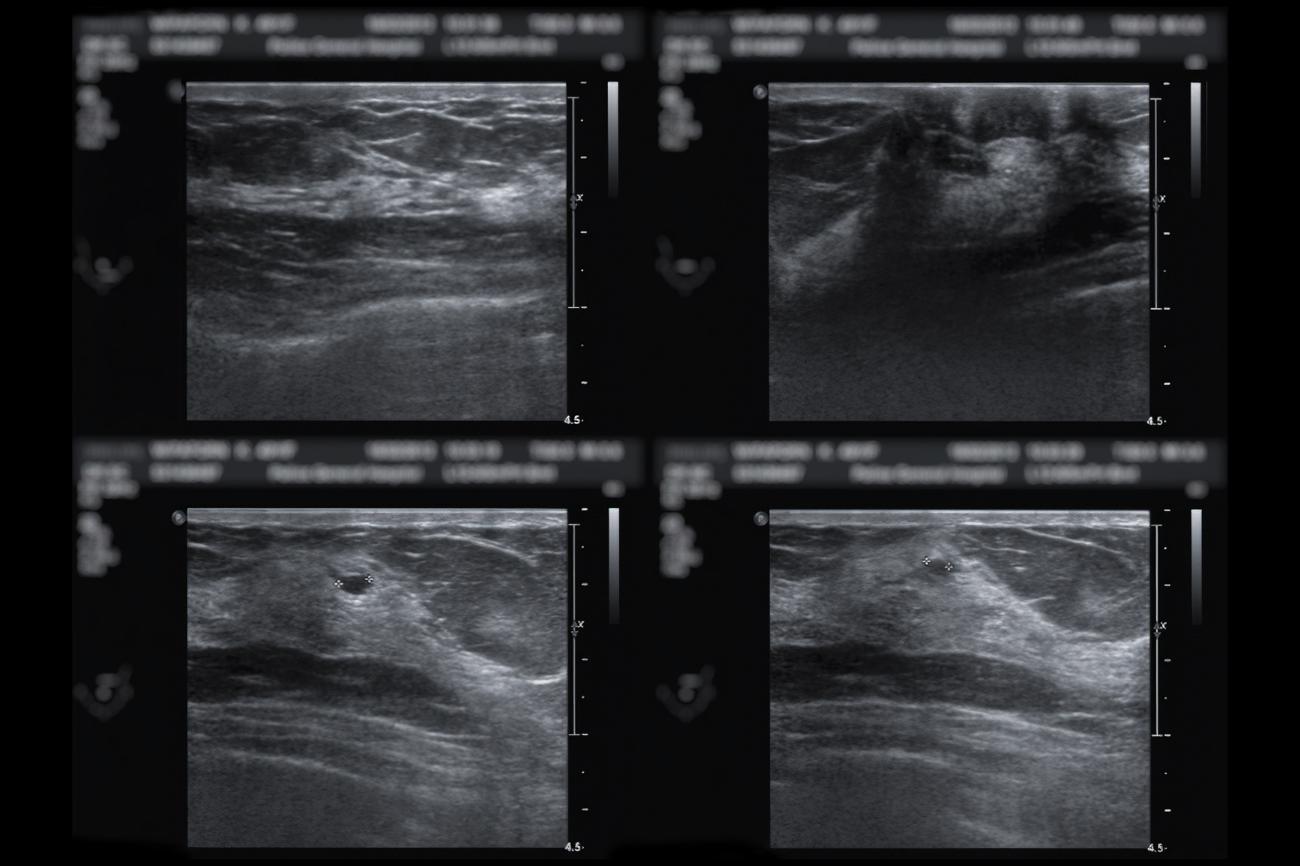

New ultrasound technology developed at Johns Hopkins can distinguish fluid from solid breast masses with near perfect accuracy, an advance that ...